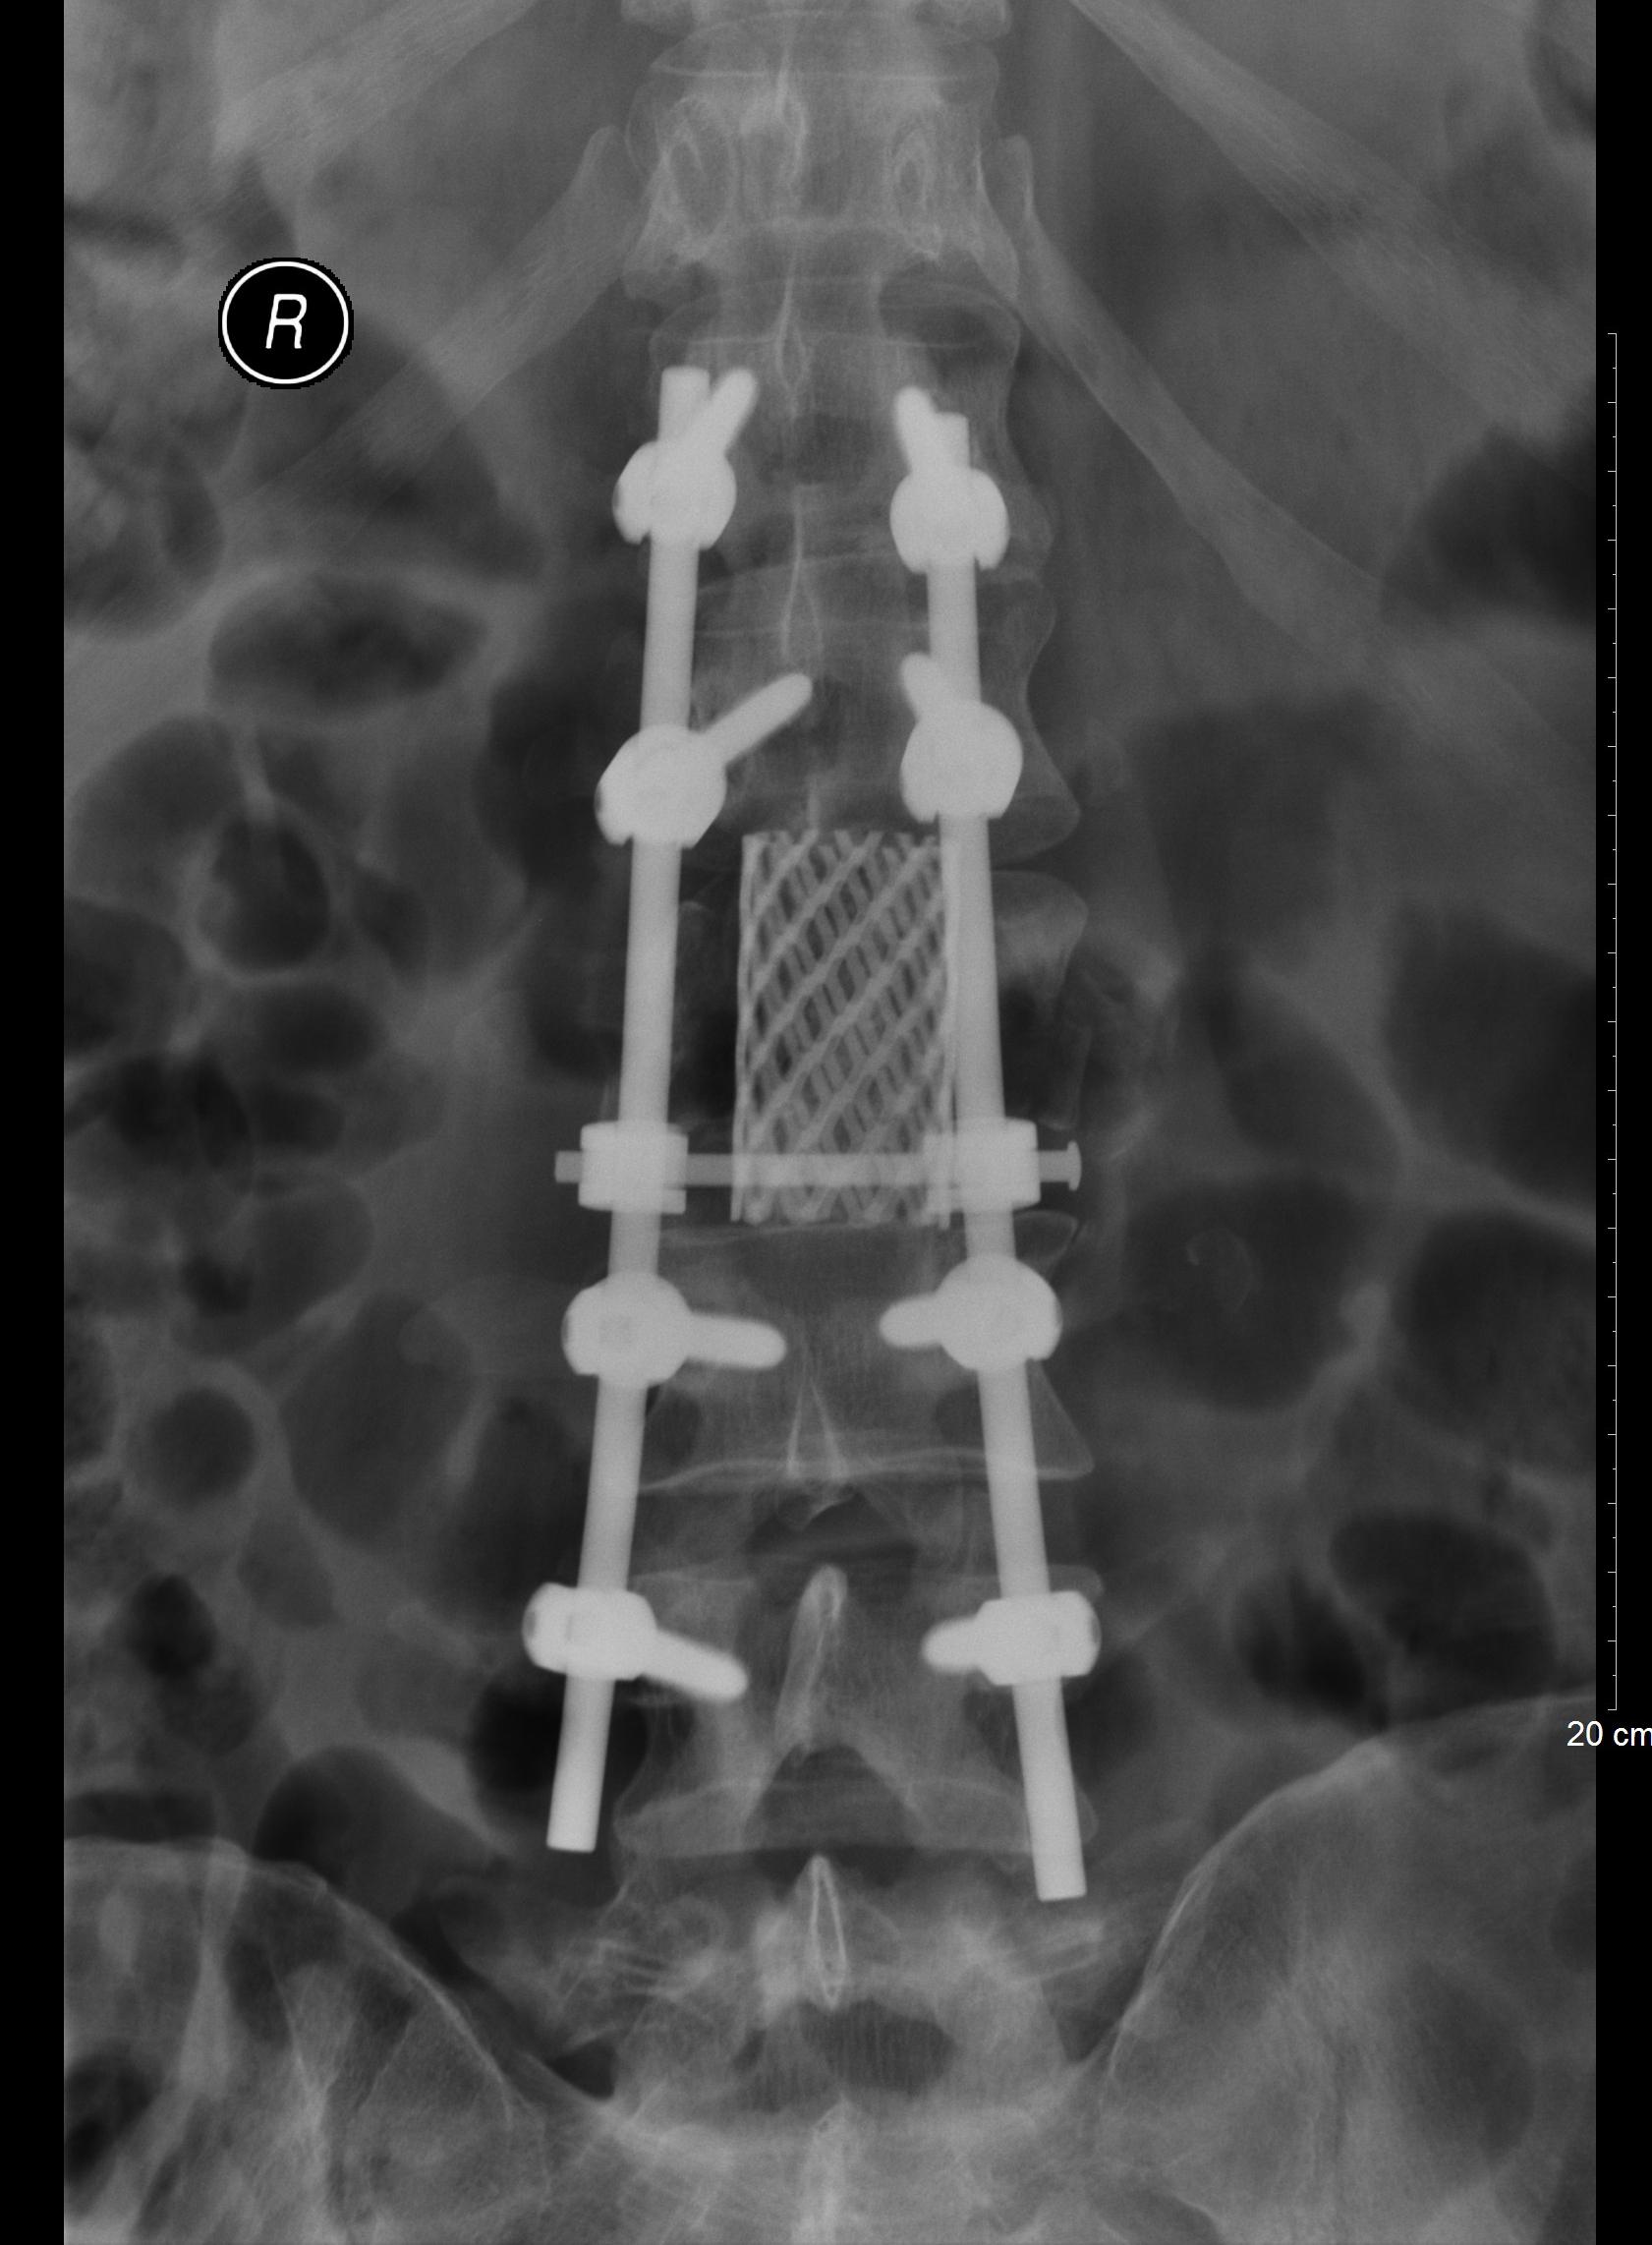

待患者病情平稳,行腰椎椎管减压和内固定融合手术,以及左股骨干髓内钉内固定手术。

术后腰椎X片